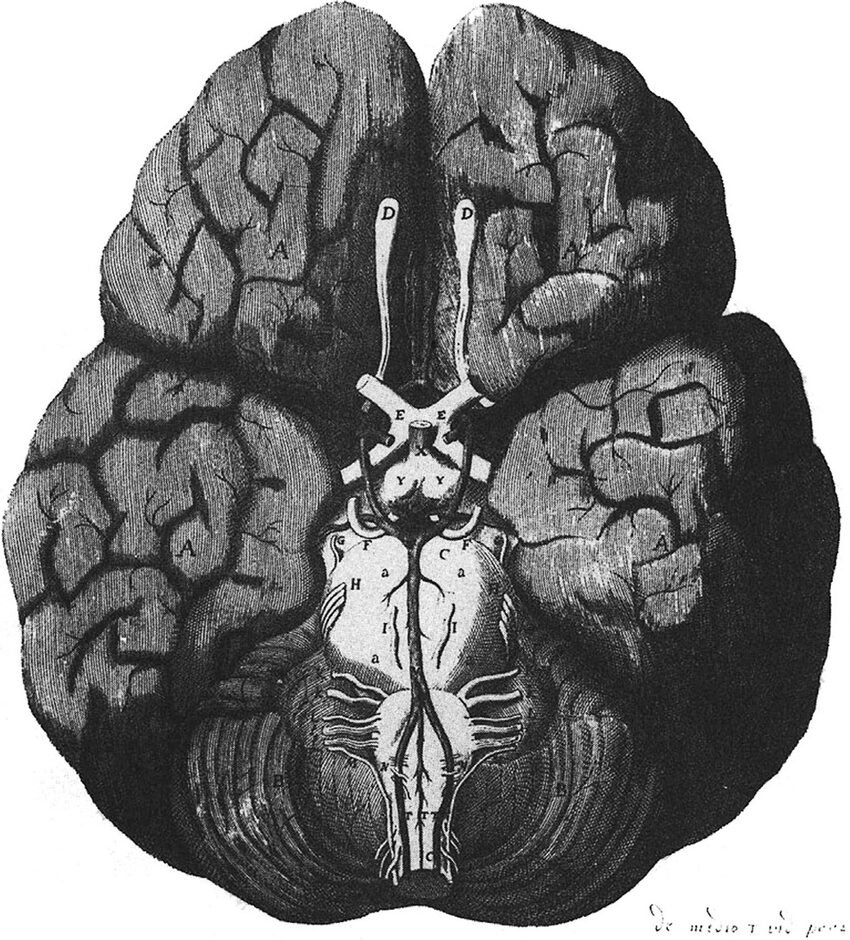

2.脳中心説の確立(17世紀)

中心人物

- Thomas Willis

- René Descartes

転換点:精神機能を脳機能として理解。